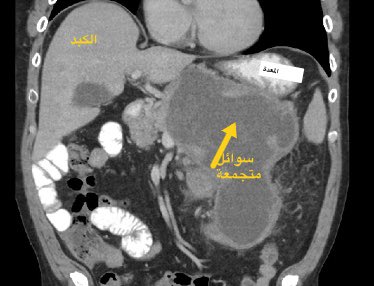

#مرض_من_العيادة (سلسلة توعوية اسبوعية)    مريض في ال ٥٠ من العمر يعاني من الم وانتفاخ في اعلى البطن. يشرب الخمور. سبق علاجه من التهابات البنكرياس النا